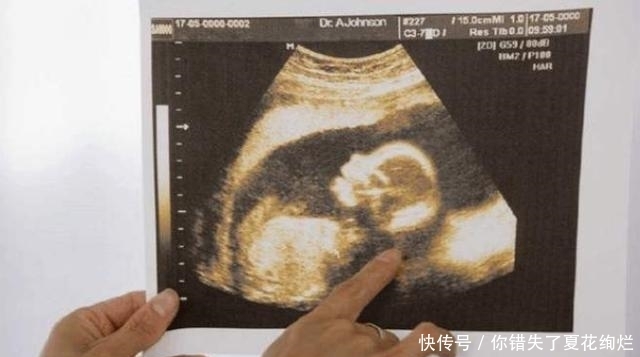

小金怀孕6个月身体一直很好,胎儿也是稳定的时期,但是家人对她的管束却越来越严。